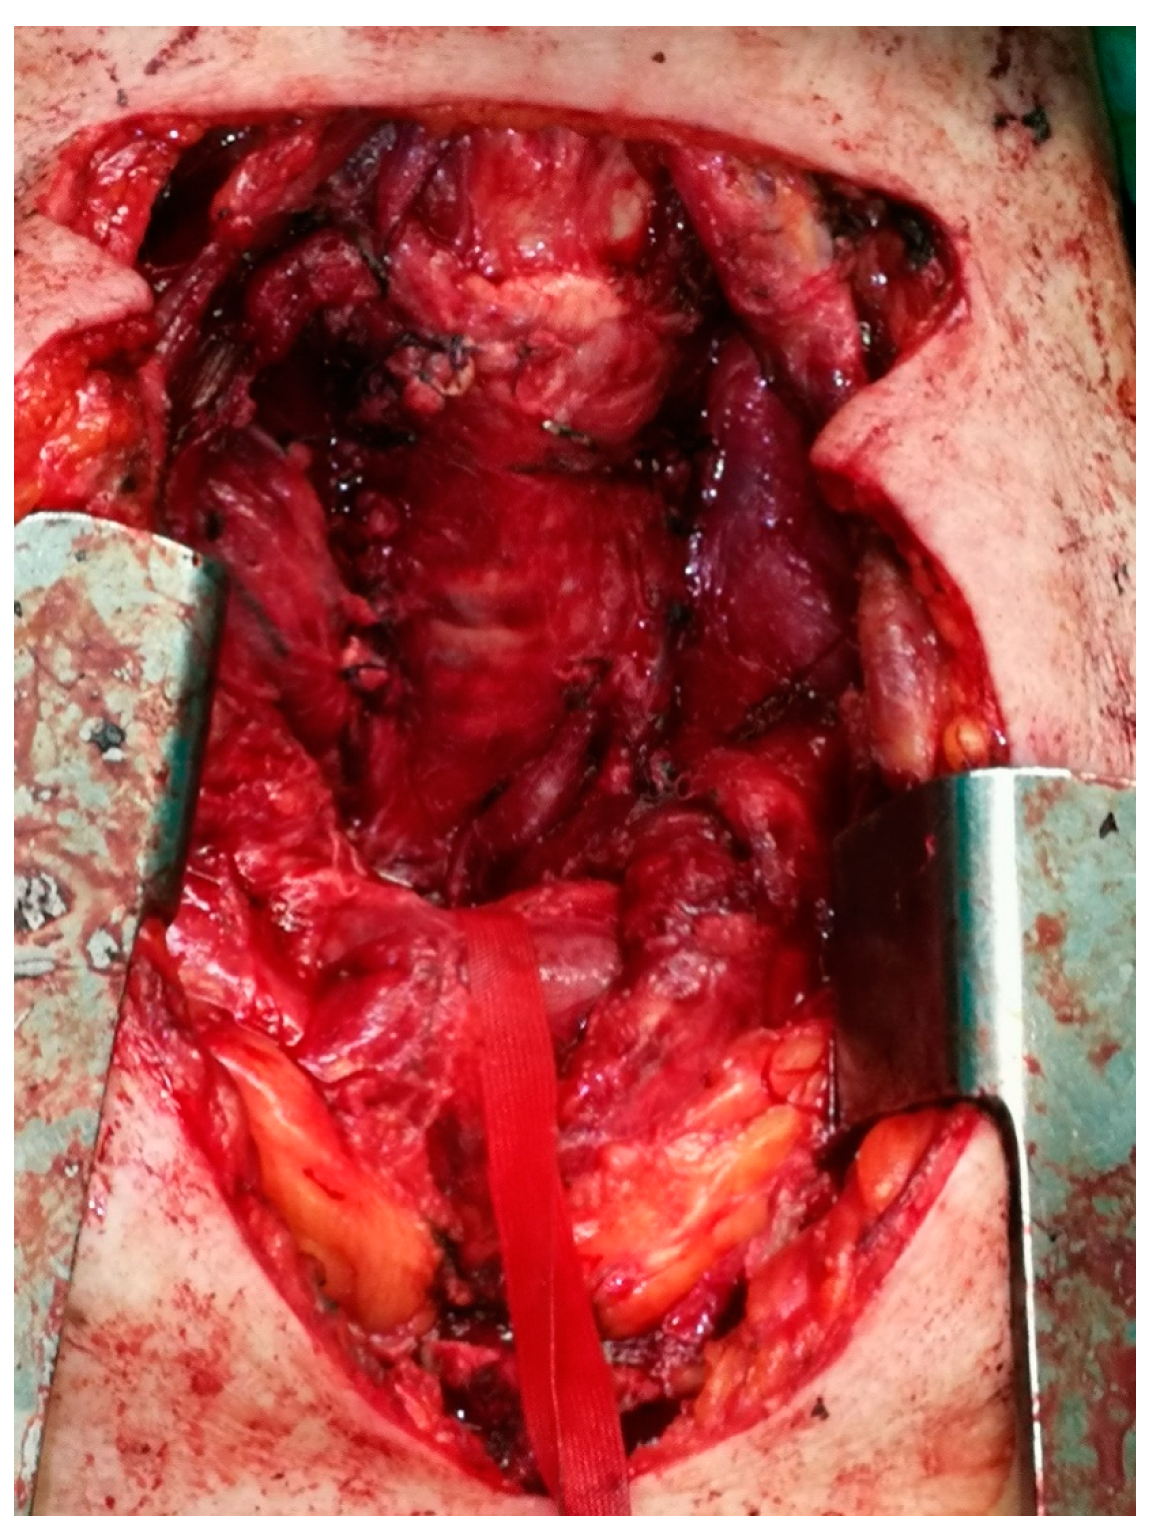

Cardiopulmonary Arrest Caused by Large Substernal Goiter—Treatment with Combined Cervical Approach and Median Mini-Sternotomy: Report of a Case

Koulouris, C.; Paraschou, A.; Manaki, V.; Mantalovas, S.; Spiridou, K.; Spiridou, A.; Laskou, S.; Michalopoulos, N.; Radu, P.A.; Cartu, D.; et al. Cardiopulmonary Arrest Caused by Large Substernal Goiter—Treatment with Combined Cervical Approach and Median Mini-Sternotomy: Report of a Case. Medicina 2021, 57, 303. https://doi.org/10.3390/medicina57040303